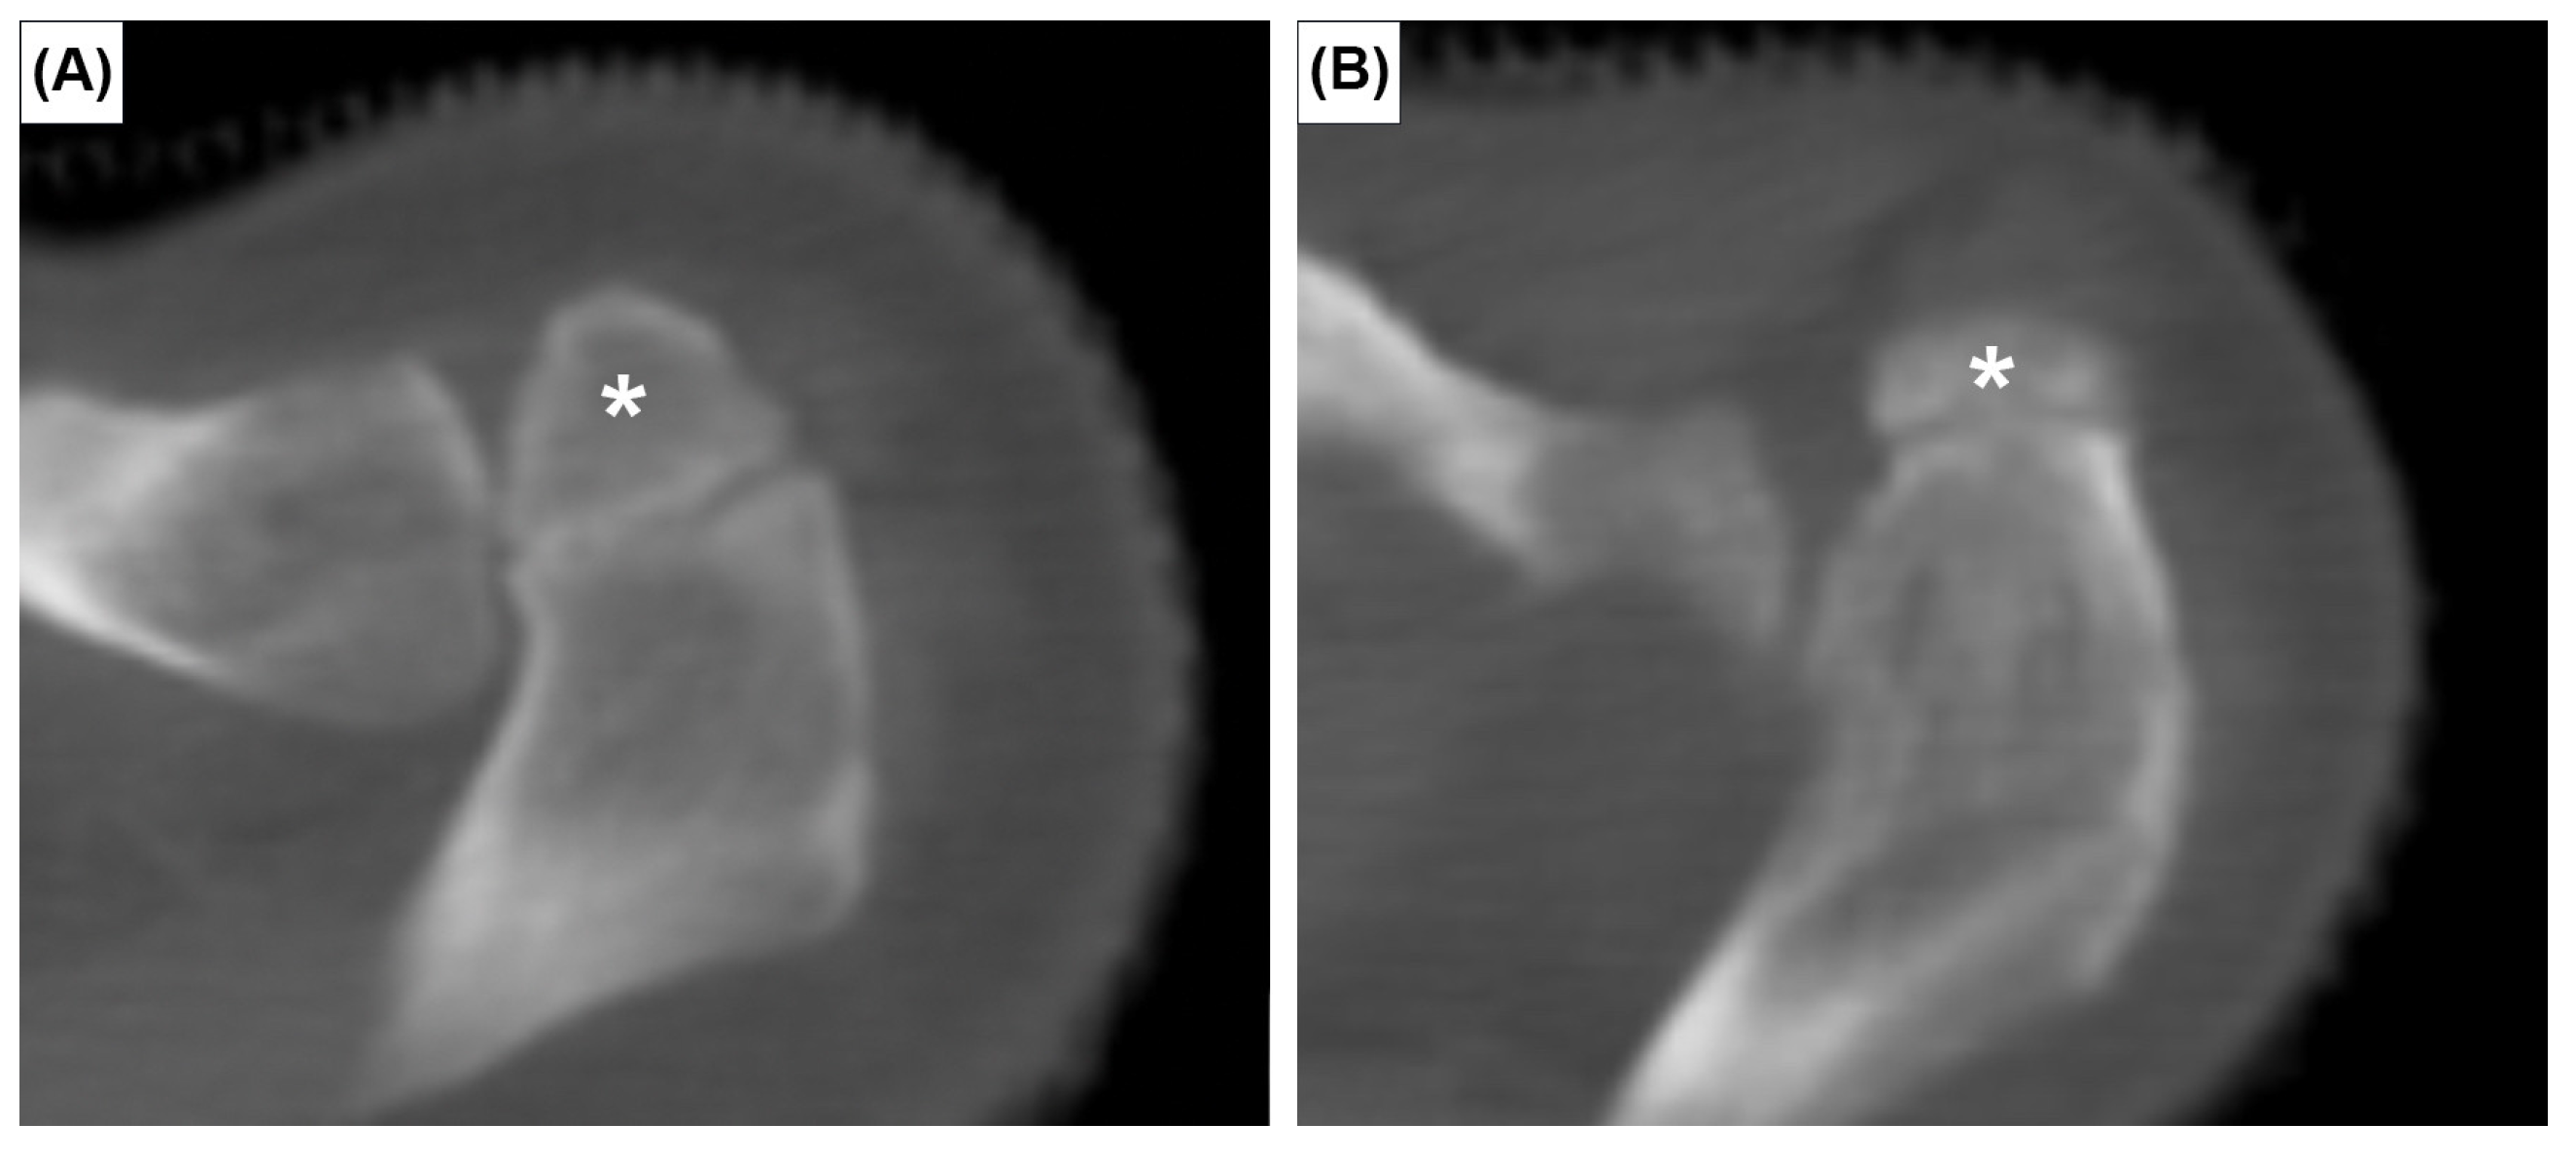

The prevalence of the six anatomical variations are presented in Table 1. Cohen’s ϰ value was 0.94 for all variants. However, after discussion and consultation with an expert radiologist, Cohen’s ϰ reached 1.00. The OA was observed in 20 patients, a crude prevalence of 3.3%. It was bilateral in 5 patients (25%) and unilateral in 15 (75%). Out of 1212 clavicles investigated, the true prevalence of OA was 1.9% (23 cases). The OA was classified as meso-acromion (Figure 1A) and pre-acromion (Figure 1B) in 19 (82.6%) and 4 (17.4%) acromia, respectively. The meta-acromion type was not observed.

Figure 1. Axial CT images showing two types of os acromiale: meso-acromion (A) and pre-acromion (B). Asterisks indicate the os acromiale.